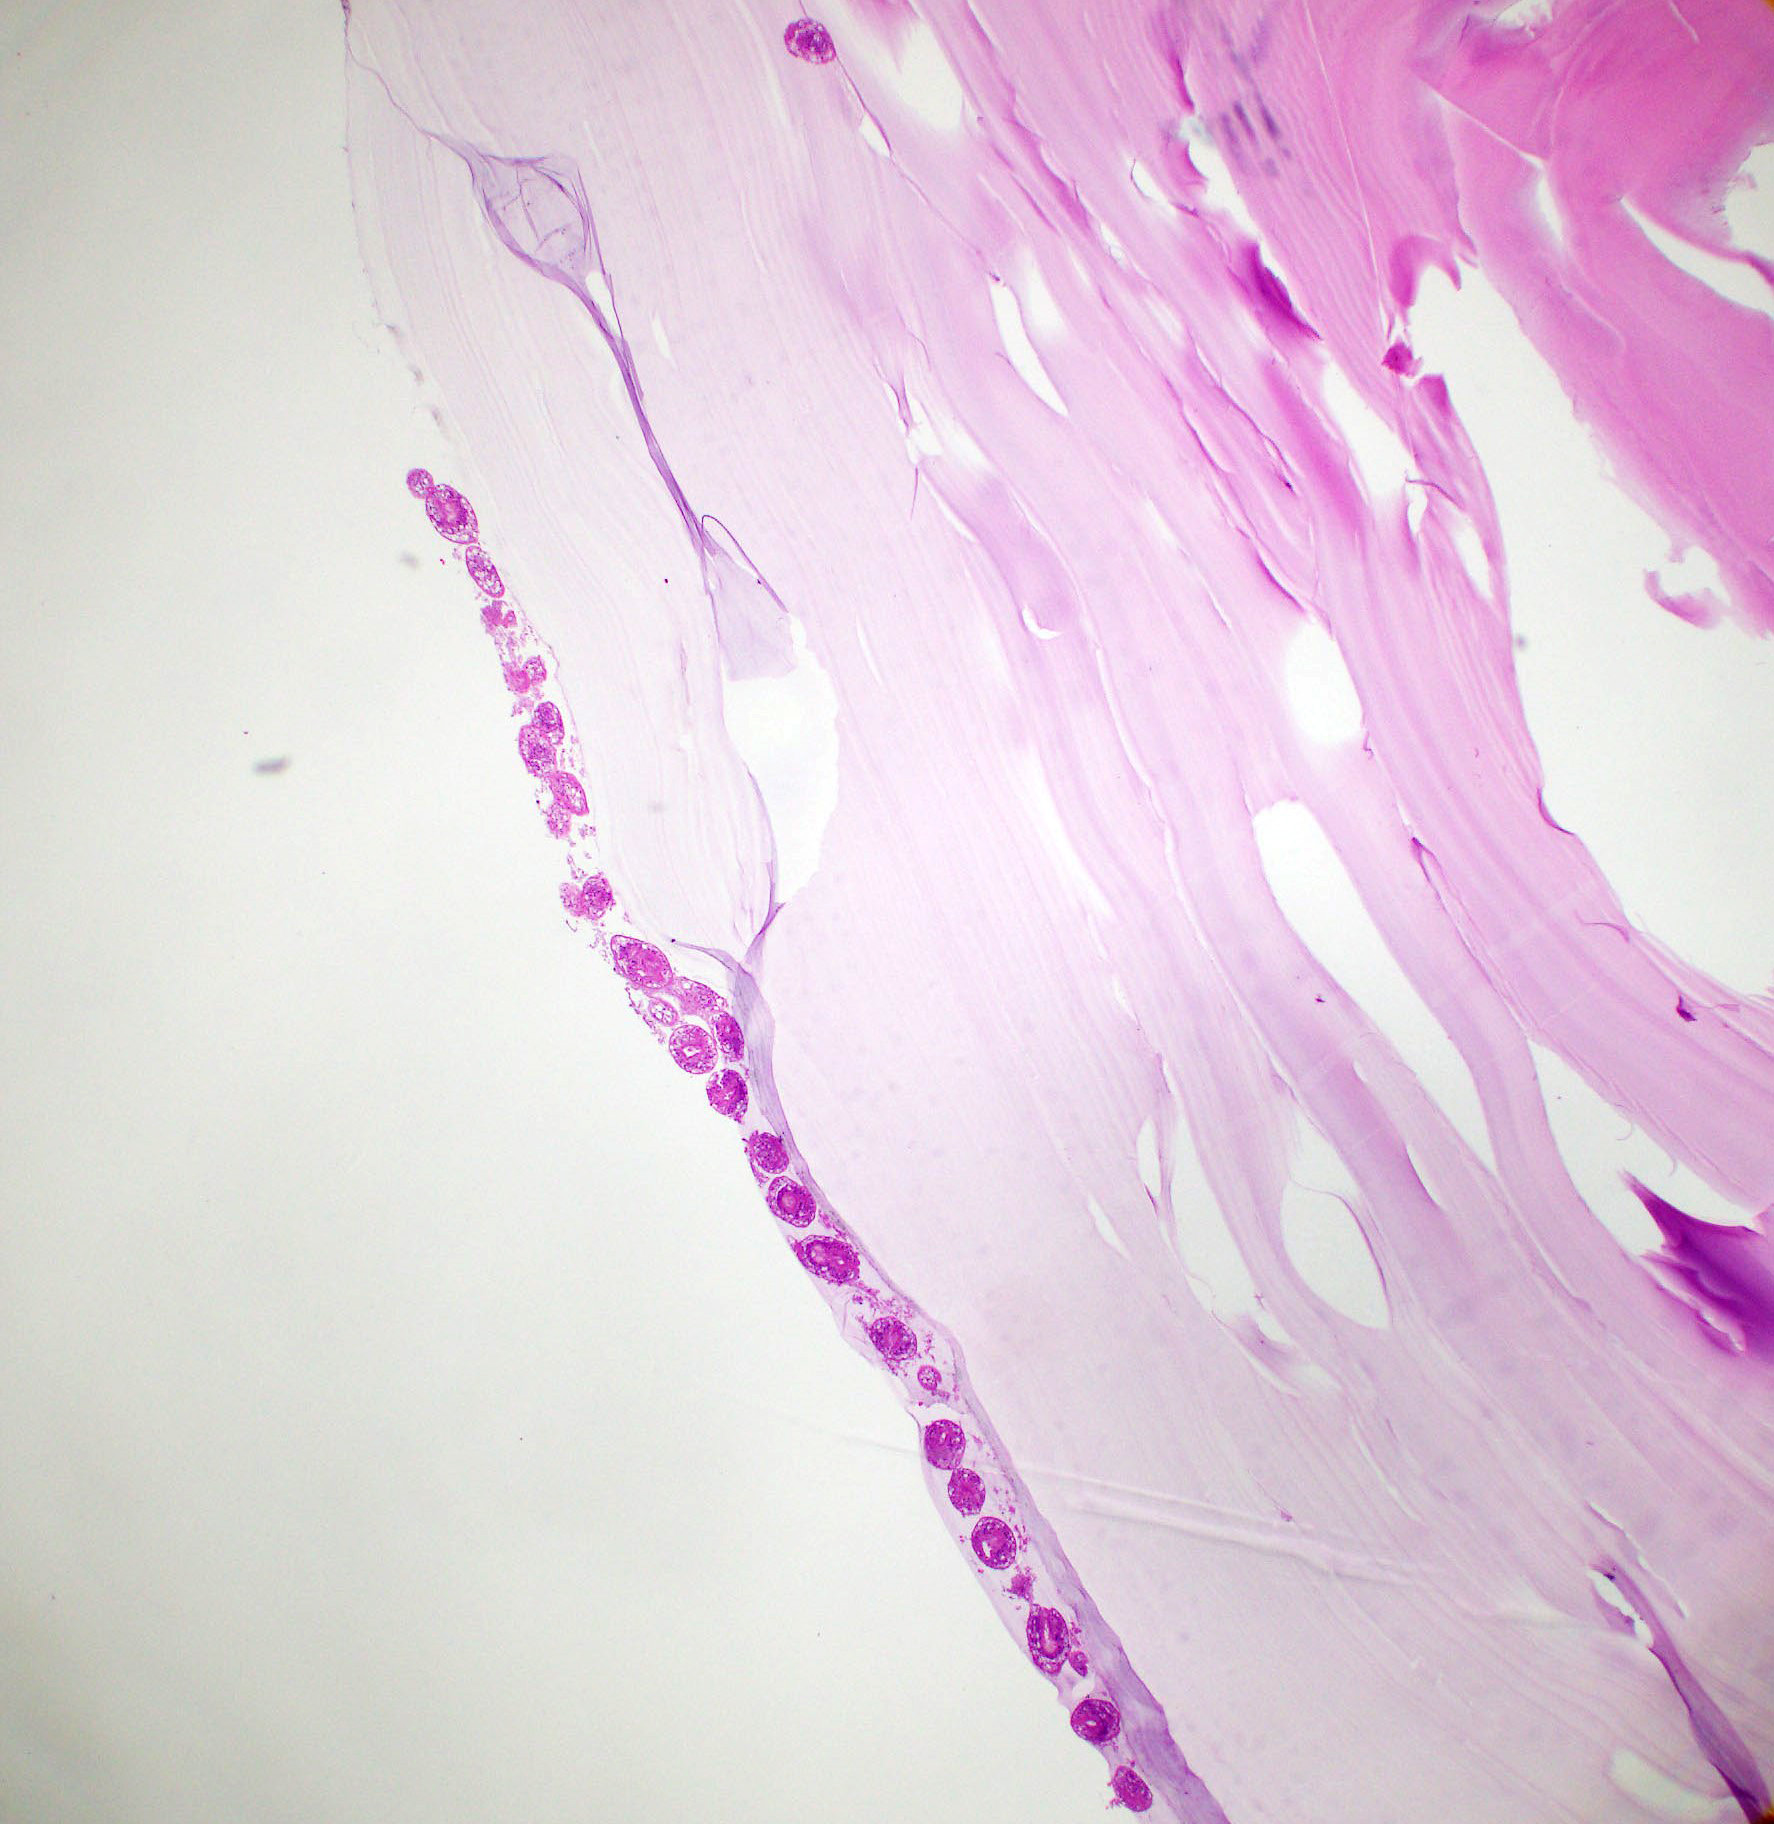

Microscopic (histologic) description

- E. granulosus

- Cyst wall has 3 structural components:

- Outer acellular laminated membrane (1 mm thick)

- Germinal membrane (a transparent nucleated lining)

- Protoscolices, attached to the membrane and budding from it

- Protoscolices are ovoid and contain hooklets (birefringent under polarized light) and a sucker

- Outer fibrotic layer with granulation tissue with increased eosinophils also exists

Microscopic (histologic) images